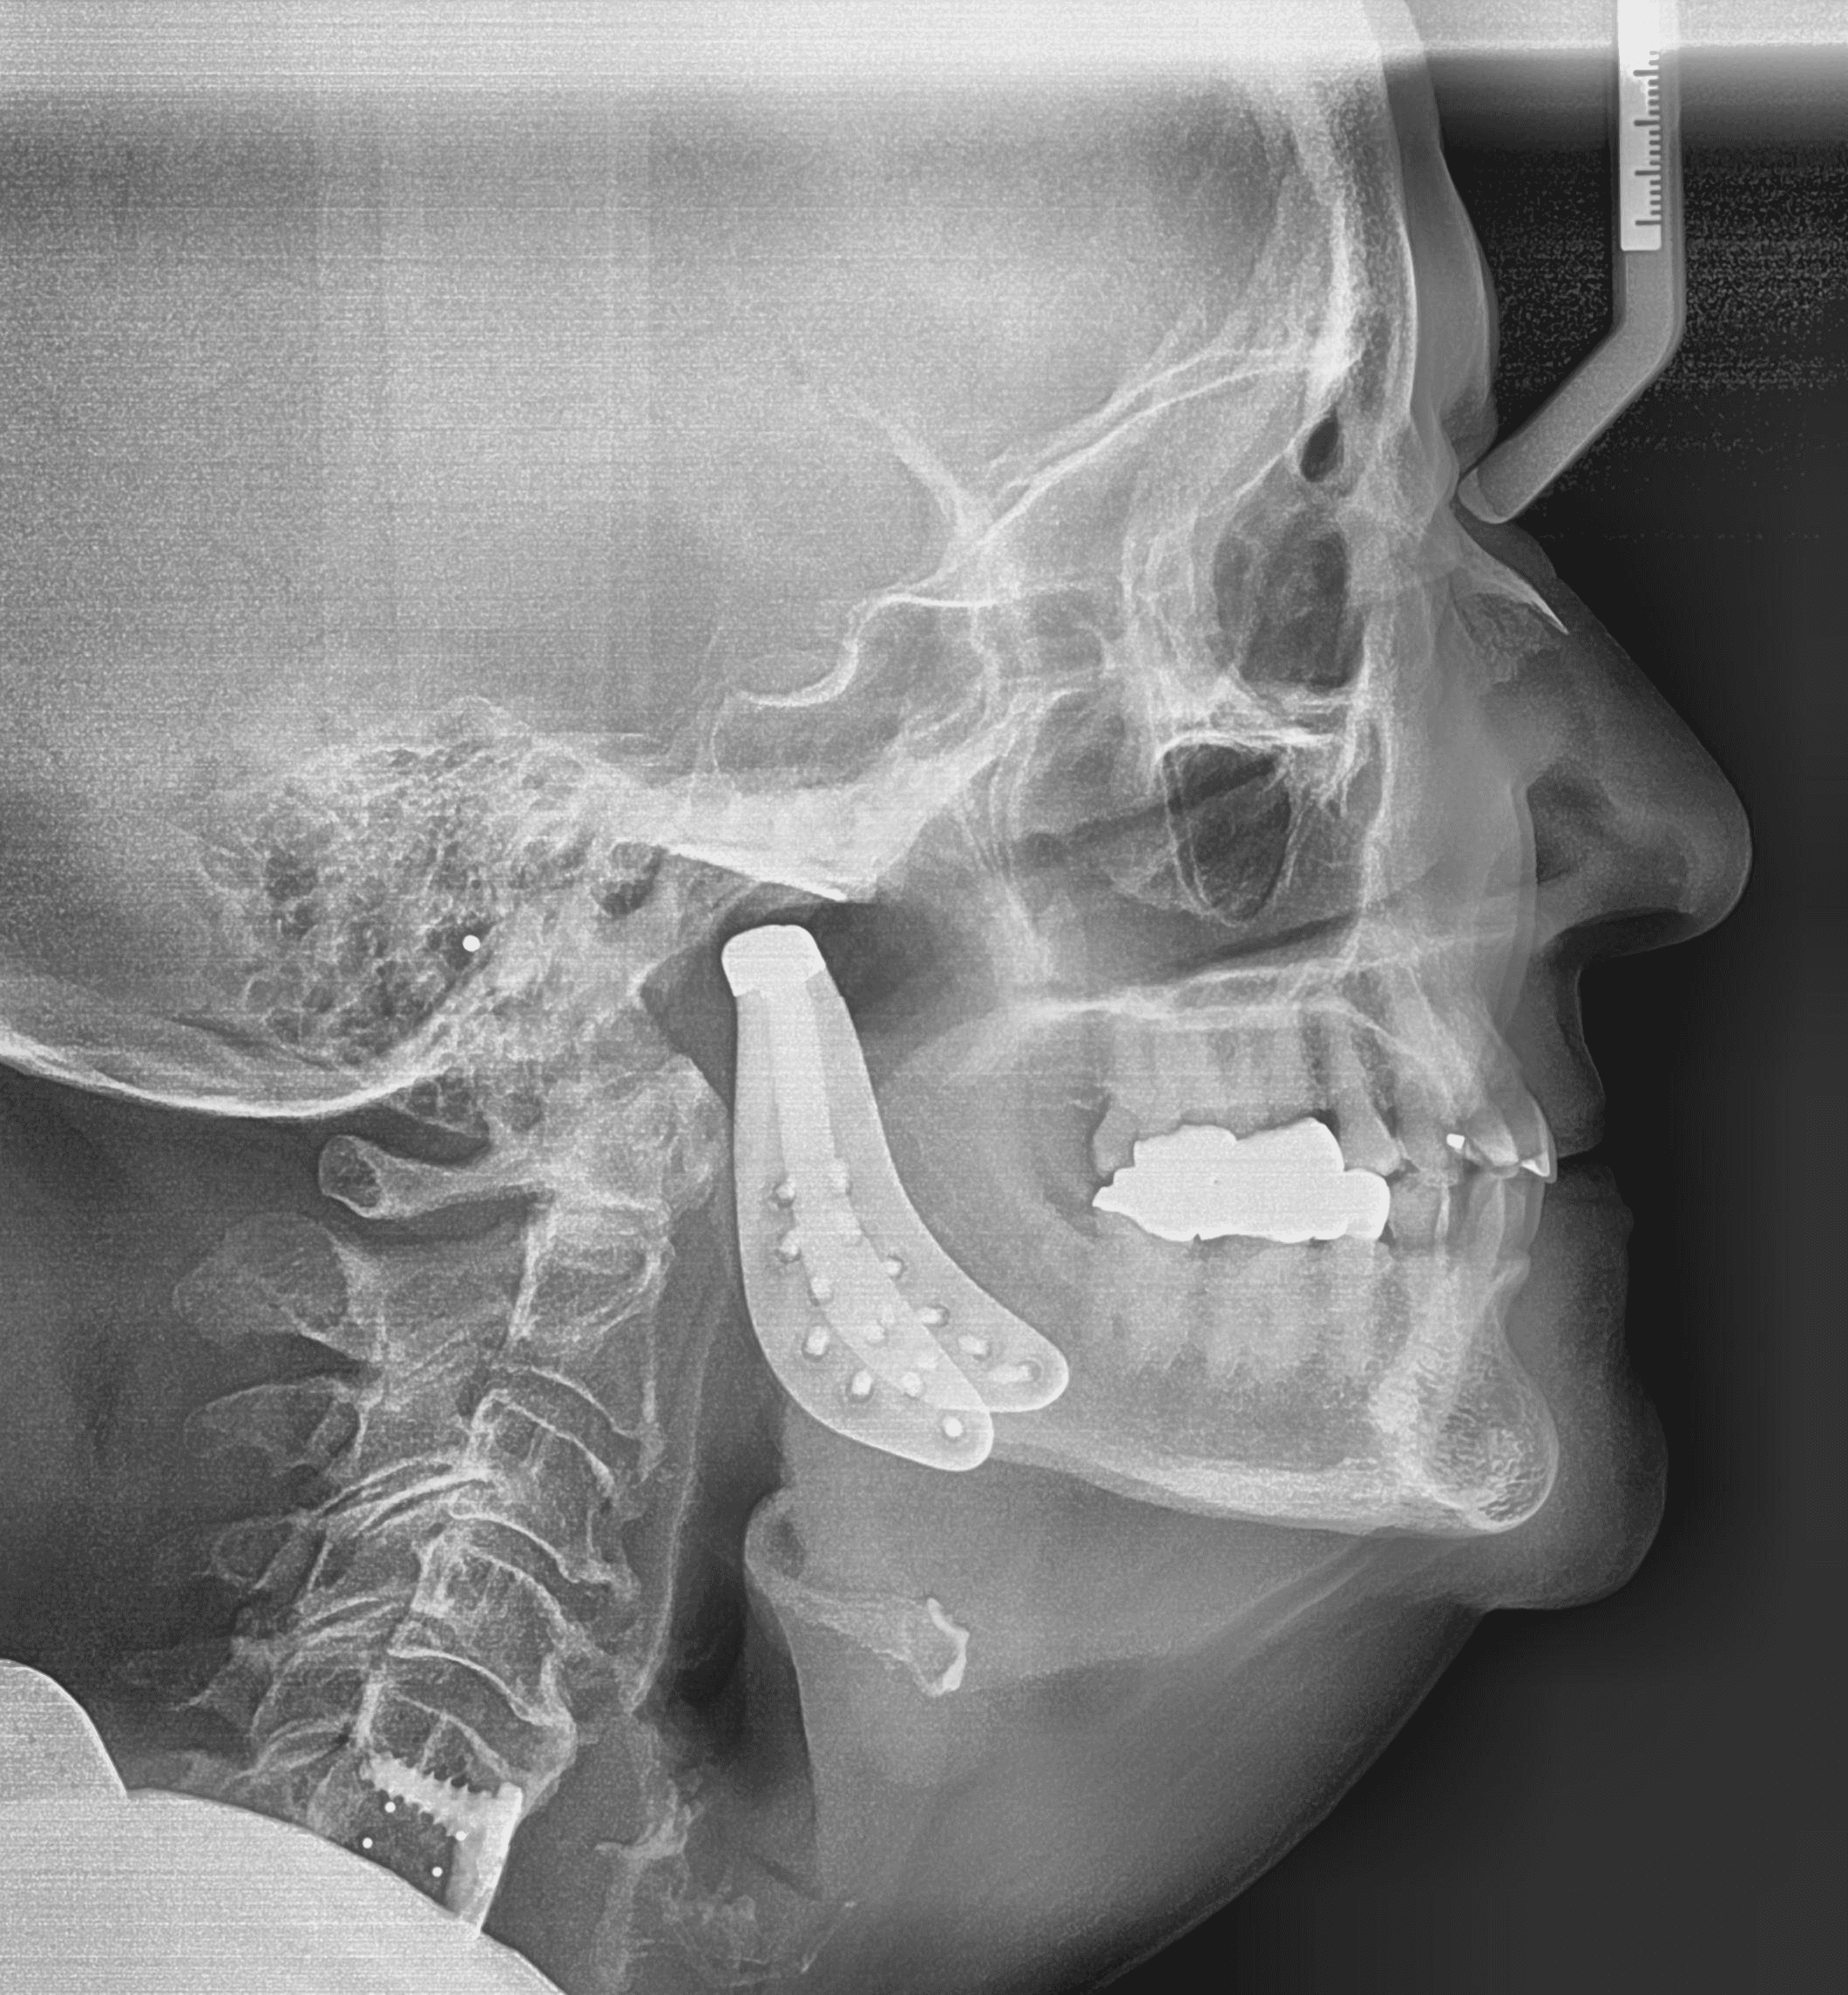

Diganosis: Complex pre-restorative treatment to open bite, mild to moderate upper and lower crowding, incisal wear in both arches

Adjuncts: Bite ramps, attachments, IPR

X-RAYS